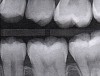

Fig 3. Three thin soft dental picks were used simultaneously for SDF proximal surface saturations in a teenaged patient (Fig 3). After 60 seconds, the treated regions were covered with 5% fluoride varnish (Fig 4). A comparison can be seen of pre-SDF-treatment bitewing films (Fig 5) and 8-month post-SDF bitewing films (Fig 6) for the patient shown in Fig 3 and Fig 4. Radiolucencies were similar or improved, except for contact of maxillary first and second molars.

Figure 3

Fig 5. Three thin soft dental picks were used simultaneously for SDF proximal surface saturations in a teenaged patient (Fig 3). After 60 seconds, the treated regions were covered with 5% fluoride varnish (Fig 4). A comparison can be seen of pre-SDF-treatment bitewing films (Fig 5) and 8-month post-SDF bitewing films (Fig 6) for the patient shown in Fig 3 and Fig 4. Radiolucencies were similar or improved, except for contact of maxillary first and second molars.

Figure 5

Interproximal insertion of SDF is demonstrated in different patients in Figure 3 through Figure 11. Various diameters and brands of soft dental picks may be used depending on the closeness of the proximal surfaces and ease of insertion; for example, some picks are designed for use in wider spaces between teeth. This protocol also offers versatility. Figure 3, for example, shows the simultaneous use of three thin soft dental picks to saturate proximal surfaces with SDF in a teenaged patient; the treated regions were subsequently covered with fluoride varnish (Figure 4). This patient was initially treated in April 2019 (Figure 5), with an identical re-application 3 months later. As shown in Figure 6, the December 2019 bitewing film revealed good results with the possible exception of the contact regions of the maxillary first and second molars. New SDF application was completed in the December appointment.